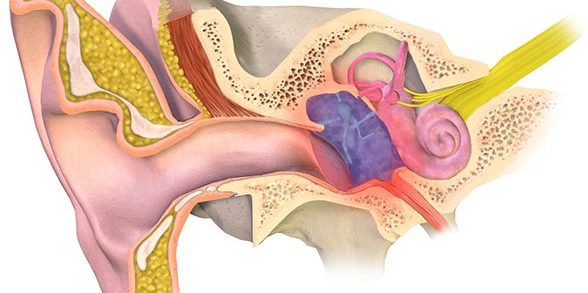

Uyku Apnesi Nedir? Uyku apnesi, uyku sırasında şiddetli horlama ile birlikte 10 saniyeden daha uzun bir süre solunumun durmasıdır. Ciddiye alınması gereken bir hastalık olan uyku apnesi, oldukça sık görülen bir durumdur. Uyku Apnesinin Nedenleri Nelerdir? Uyku apnesinin en sık görülen nedeni, boğaz ve yumuşak damaktaki kasların uyku sırasında havanın geçiş yolunu kapatacak şekilde gevşemesidir.…

- Horlama ve Uyku Apnesi: Uyku sırasında solunum sorunlarına bağlı olarak gelişen durumlardır.